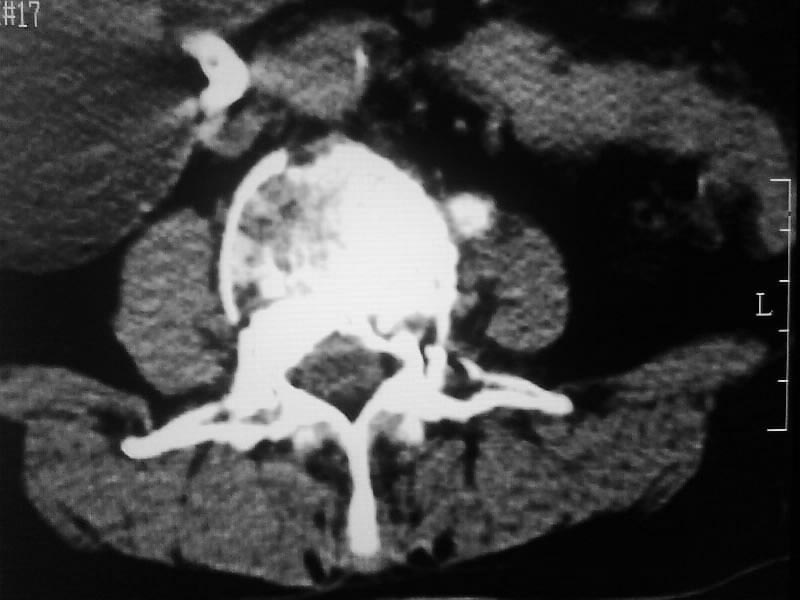

定位相示l2呈楔形改变(ct示陈旧性骨折改变,图像未传),l4.5椎体融合,以下是l4.5ct平扫.请各位看看,

考虑结核(有破坏、硬化及死骨)。

1、三四椎体结核,2、水平骶椎。

1、l1压缩性骨折(陈旧性)。

2、l3、4椎体结核。

就是腰1压缩性骨折,腰3\\4椎体结核(融合),水平骶椎.

支持 l1椎体陈旧性压缩性骨折;l3、4椎体结核(融合);水平骶椎。